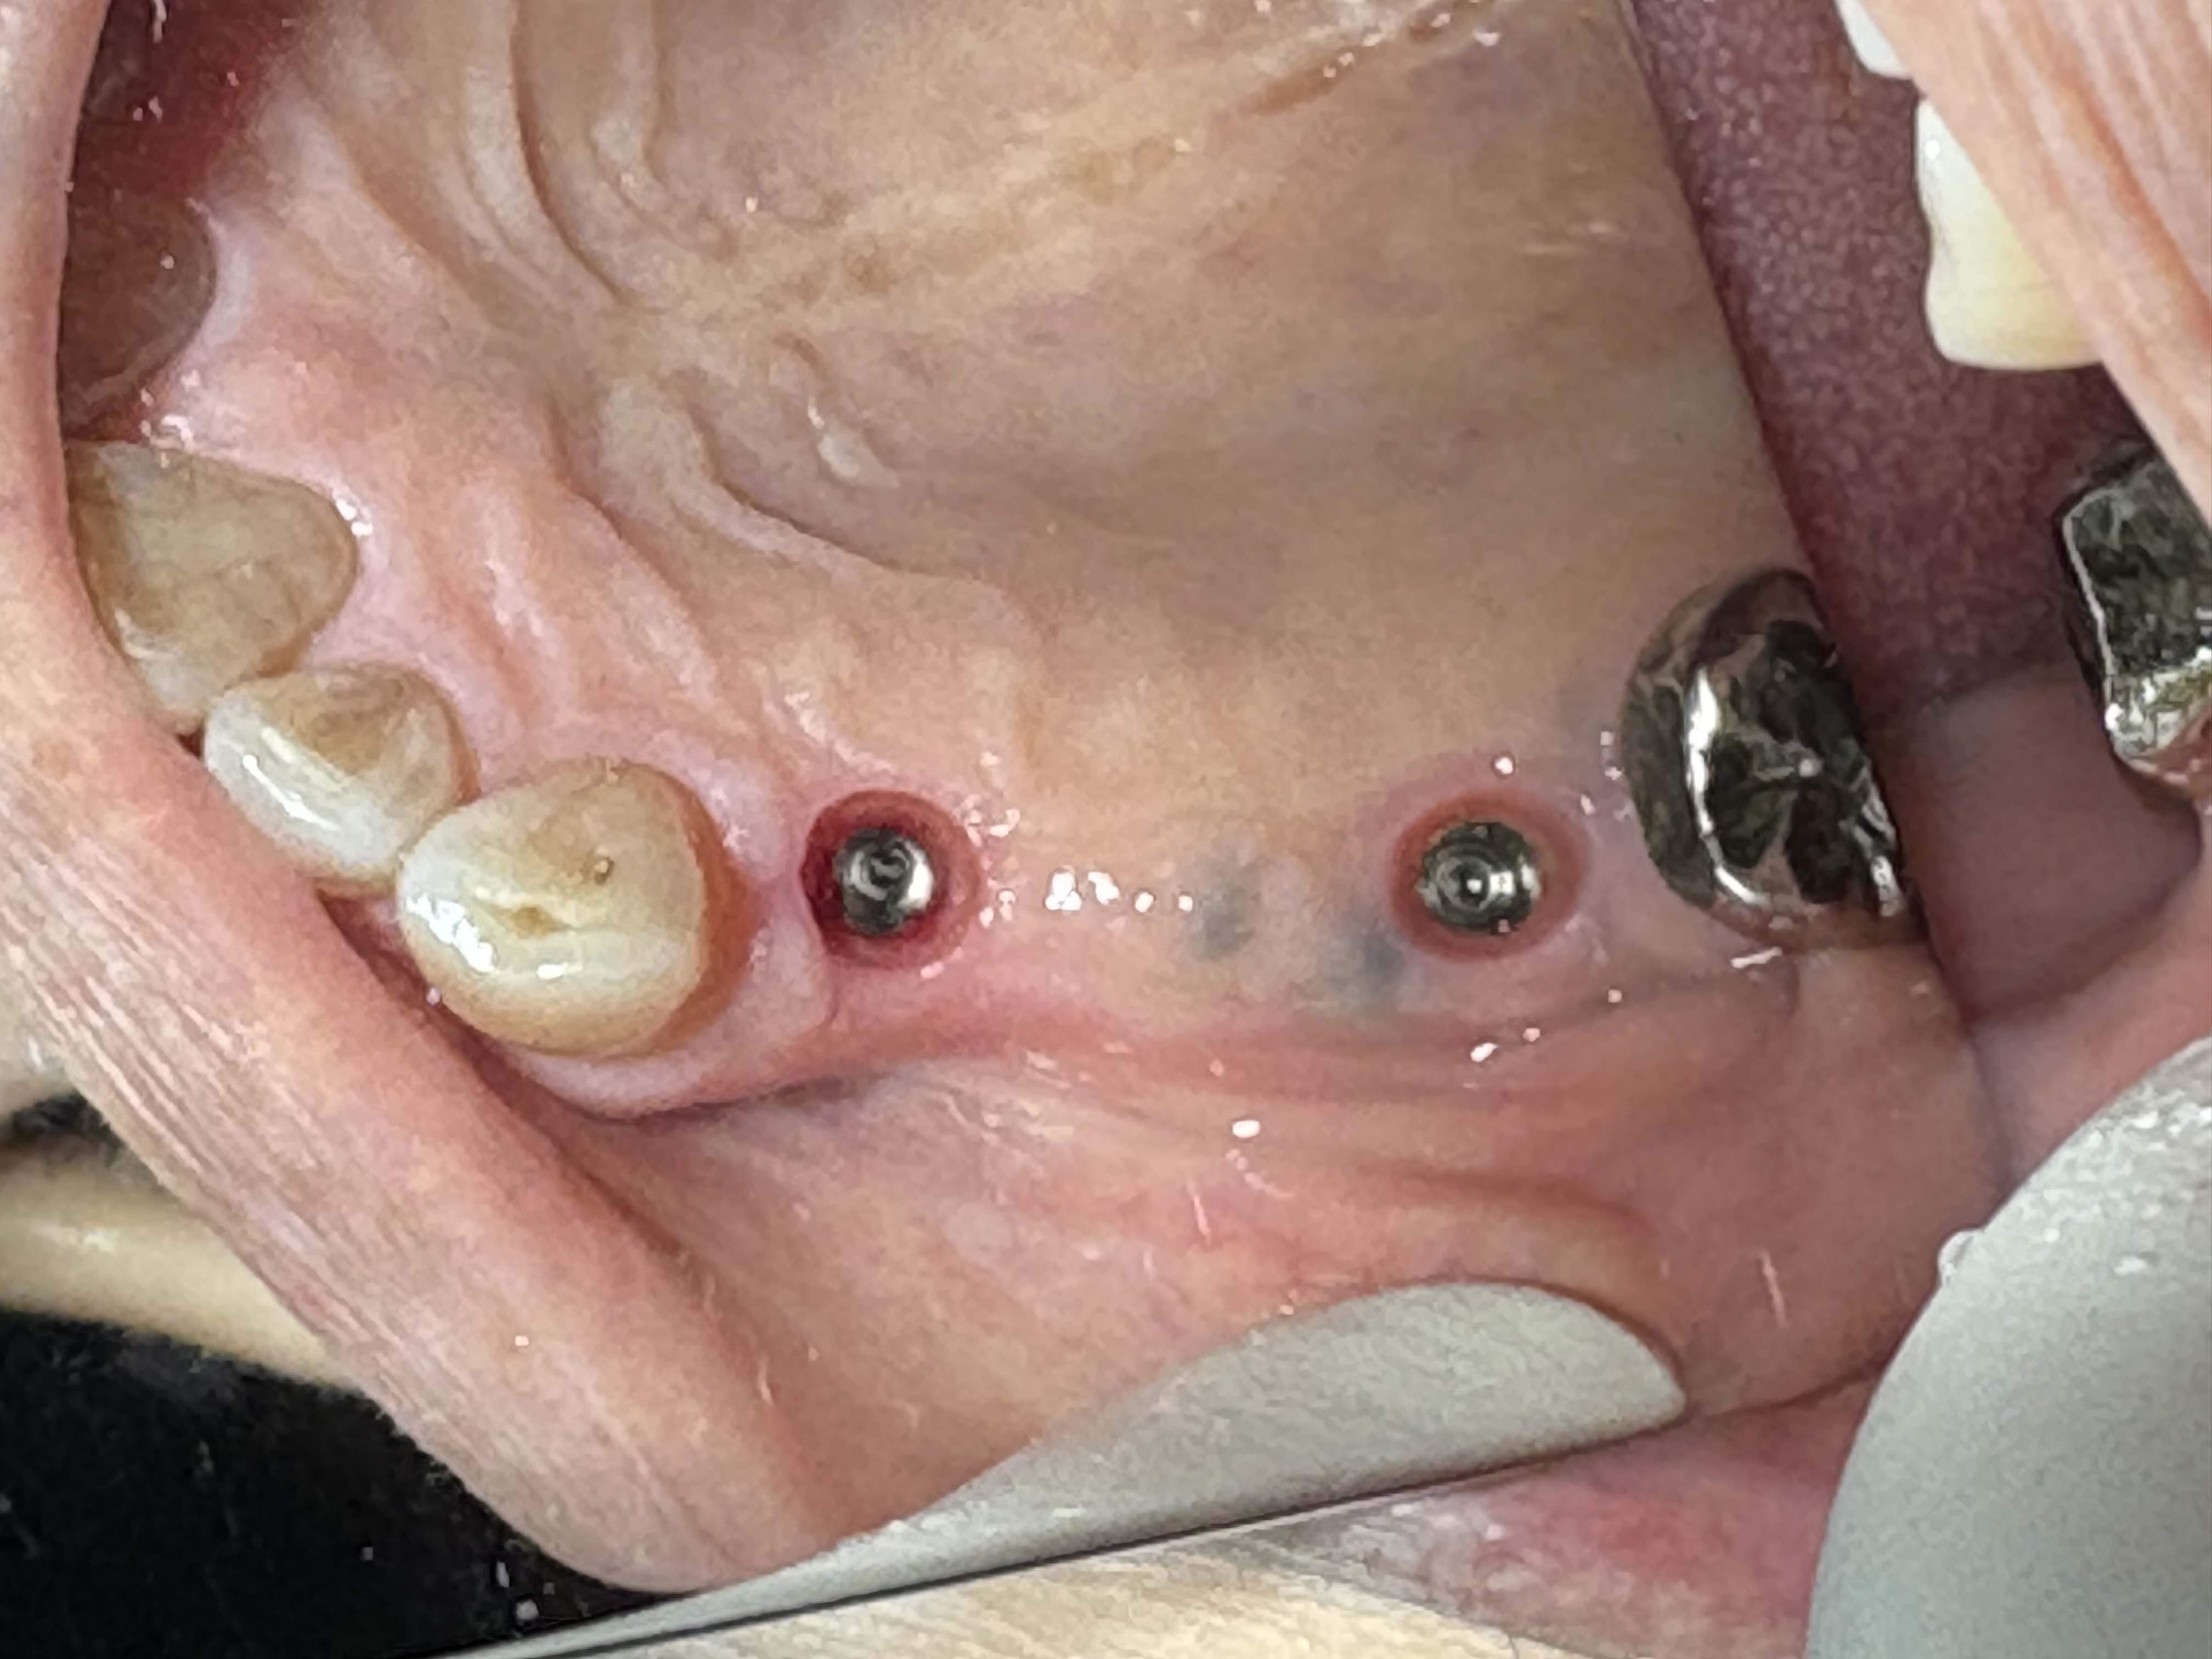

インプラント一次手術

左上4番・6番 2本埋入